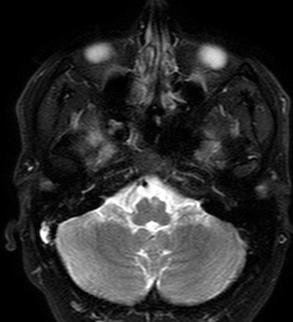

Diagnostic methodology: Narcolepsy

Current diagnostic method: PSG, next day multiple sleep latency test (MSLT)

mean sleep latency ≤8 minutes (MSLT)

≄2 SOREMPs (between PSG and MSLT)

Narcolepsy →short sleep latency, rapid transitions into REM sleep

Narcolepsy

Confirmation

ALSO poor nocturnal sleep consolidation, sleep state ambiguity, intrusion of REM (portions of REM) into other states

Can you use AI to diagnose Narcolepsy based on an overnight PSG ALONE?